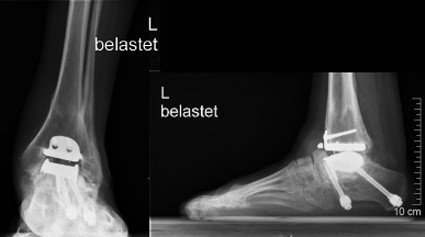

Im Jahr 2006 stellt sich die Patientin in der Fusschirurgie der Schulthess Klinik vor. Die Untersuchung zeigte ein hinkendes Gangbild mit Entlastung des linken Fusses. Der Fuss selbst zeigte eine Fehlstellung als Residuum der angeborenen Klumpfussdeformität. Das Bewegungsausmass im Bereich des oberen Sprunggelenkes betrug 5° nach oben und 10° nach unten. Das gesamte Gelenk stellte sich überwärmt und druckschmerzhaft dar. Die im Rahmen der Konsultation durchgeführten Röntgenaufnahmen zeigten, dass die untere Prothesenkomponente, welche im Bereich des Sprungbeines verankert ist, nach unten eingesunken war. Die Schraube, die diese Komponente fixiert war gebrochen. Es bestand der Verdacht einer Nekrose (=abgestorbener Knochen) im Bereich des Sprungbeines.

Mit der Patientin wurden die möglichen Optionen besprochen. Der Wechsel der Prothese erschien nicht sinnvoll, da die Verankerung der «neuen» Prothese in einem nekrotischen Knochen nicht zu einem stabilen Einwachsen des Knochens in die Prothese führen würde. Zudem waren die Aussichten auf eine Verbesserung der Gelenkbeweglichkeit nicht gegeben.

Von konservativer Seite bestanden keine zielführenden Therapieoptionen, so dass es am sinnvollsten erschien, die Prothese auszubauen und eine erneute Versteifung des oberen Sprunggelenkes durchzuführen, um stabile Verhältnisse und eine möglichst schmerzfreie Belastung zu erreichen.